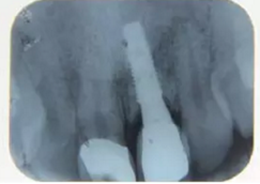

種植完成后可以通過拍攝曲面體層或是根尖片來確認(rèn)種植體的植入情況,并作為資料加以保存。

圖7 曲面體層片